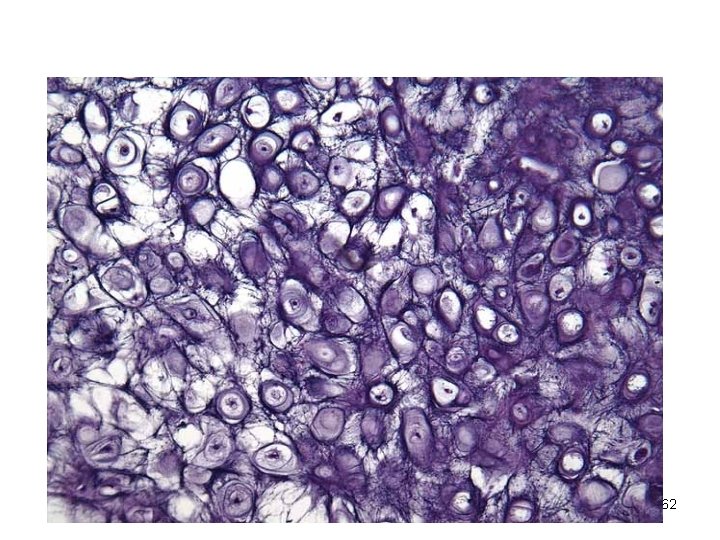

Connective Tissue: Elastic Cartilage Similar to hyaline cartilage but with more elastic fibers ¡ Maintains shape and structure while allowing flexibility ¡ Supports external ear (pinna) and the epiglottis ¡ 61

62

Connective Tissue: Fibrocartilage Cartilage Matrix similar to hyaline cartilage but less firm with thick collagen fibers ¡ Provides tensile strength and absorbs compression shock ¡ Found in intervertebral discs, the pubic symphysis, and in discs of the knee joint ¡ 63